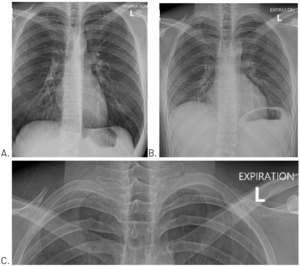

A posterior to anterior chest, posterior to anterior left rib, and left oblique rib were performed the day after examination. No fracture was evident. However, the chest image included what appeared to be a small pneumothorax at the apex of the left lung field. The attending radiologist asked that the chest x-ray be repeated with both inspiration (Figure 1A) and expiration (Figure 1B). These views confirmed the presence of a small pneumothorax at the apex of the left lung.

Since the patient was not currently experiencing respiratory distress, he was told to monitor his symptoms over the weekend, and that should any worsening occur in his pain or ability to breathe to seek emergency medical care. Four days later, a repeat chest x-ray with inspiration (Figure 2A) and expiration (Figure 2B) views was performed and showed that the pneumothorax had resolved.